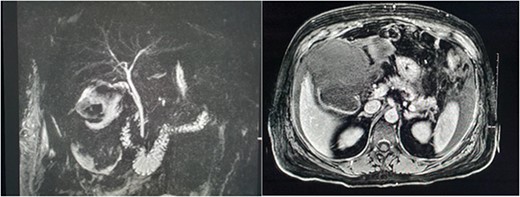

She presented on this occasion with right upper quadrant pain and collapse. Computed tomography (CT) abdomen and pelvis with intravenous contrast in the portal venous phase was performed, demonstrating perforated acute calculous cholecystitis and active haemorrhage (Fig. 1). At this point, Interventional Radiology and Upper gastrointestinal (GI) Surgery in our institution were contacted, and the patient was transferred for emergency embolization. The patient was haemodynamically unstable, so the massive transfusion protocol was commenced.

CT abdomen and pelvis with intravenous contrast in the portal venous phase was performed demonstrating perforated acute calculous cholecystitis and active haemorrhage.

Magnetic resonance imaging (MRI) of the liver and magnetic resonance cholangiopancreatography (MRCP) were performed in the following days, which demonstrated a frank rupture of the gallbladder and a patent biliary tree (Fig. 3). After a few more days, the patient became peritonitic and a further CT was performed. This demonstrated a moderate volume of peritoneal free fluid and haematoma in the gallbladder fossa (Fig. 4). Ultrasound-guided drainage of peritoneal fluid was performed producing bilious fluid. ERCP was performed, which demonstrated ongoing leak from the gallbladder fossa (Fig. 5) and allowed placement of a covered biliary stent to divert flow away from the cystic duct.

MRCP and post contrast MRI images demonstrating the wide mouthed frank disruption of gallbladder wall.